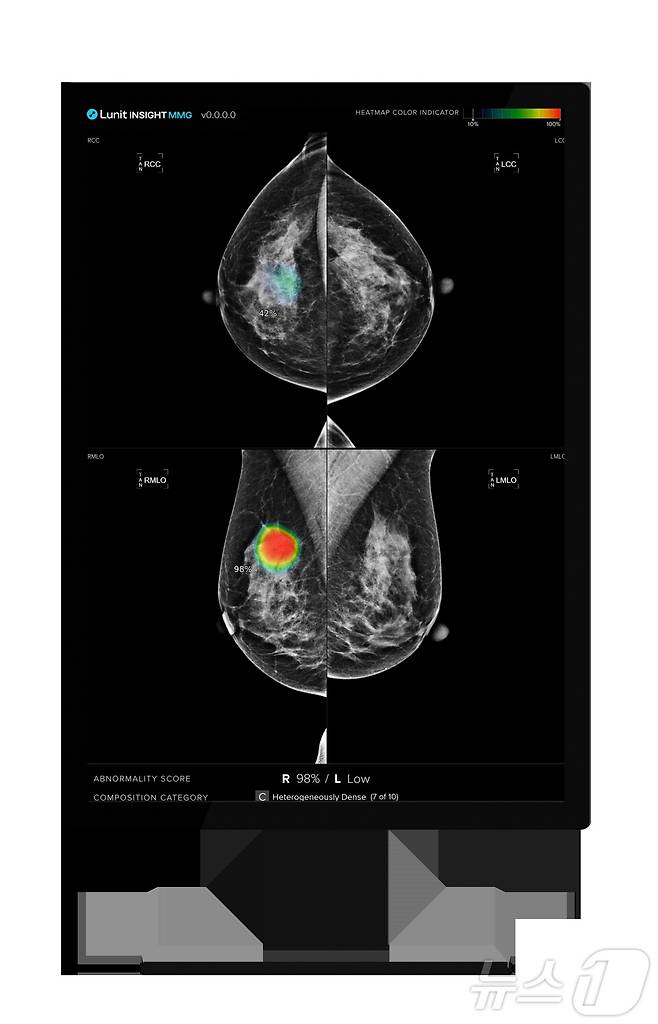

의료 인공지능(AI) 기업 루닛(328130)은 호주 뉴사우스웨일스(NSW)주 정부의 유방암 검진 프로그램 '브레스트 스크린 NSW'(BSNSW)에서 유방촬영술 AI 영상분석 솔루션 '루닛 인사이트 MMG'의 실제 임상 운영을 시작했다고 9일 밝혔다.

(서울=뉴스1) 황진중 기자 = 의료 인공지능(AI) 기업 루닛(328130)은 호주 뉴사우스웨일스(NSW)주 정부의 유방암 검진 프로그램 '브레스트 스크린 NSW'(BSNSW)에서 유방촬영술 AI 영상분석 솔루션 '루닛 인사이트 MMG'의 실제 임상 운영을 시작했다고 9일 밝혔다.

루닛은 지난 2022년 하반기부터 총 3단계에 걸쳐 BSNSW 프로젝트를 운영해 왔다. 1단계에서는 약 65만 건의 유방촬영술 영상을 분석하며 AI 기술의 정확도와 신뢰도를 입증했다. 2단계에서는 약 20만 건의 검진 데이터를 활용해 실제 임상 적용을 위한 최적화와 유효성 검증 작업(Prospective Validation)을 수행했다.

이번에 돌입한 3단계는 최종 단계이자, 실제 의료 현장에서의 운영 단계다. 루닛 인사이트 MMG는 검진을 받는 50~59세 여성을 대상으로 연간 약 3만 1000건의 유방촬영술 검사 판독을 보조할 예정이다. 이번 단계 검증을 통해 성과가 최종 확인되면, 루닛은 추가 입찰 없이 2029년까지 향후 5년간 BSNSW의 운영권을 재수주하게 된다. 이에 따라 안정적으로 매출이 증가할 것으로 전망된다.